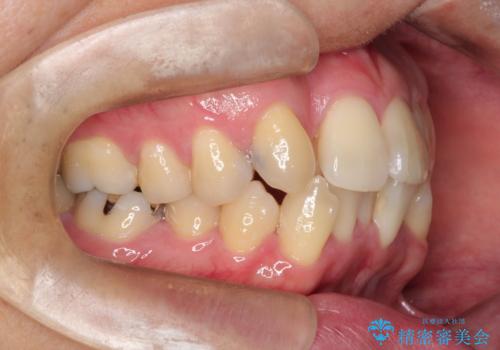

正面から見たときに右上2が全く見えないくらい、右上2が後ろに引っ込んでいる状態でしたが綺麗に並べる事が出来ました。

笑った時のスマイルラインもかなり綺麗になり大変ご満足いただく事が出来ました。

顔貌に対して歯の正中も合いました。